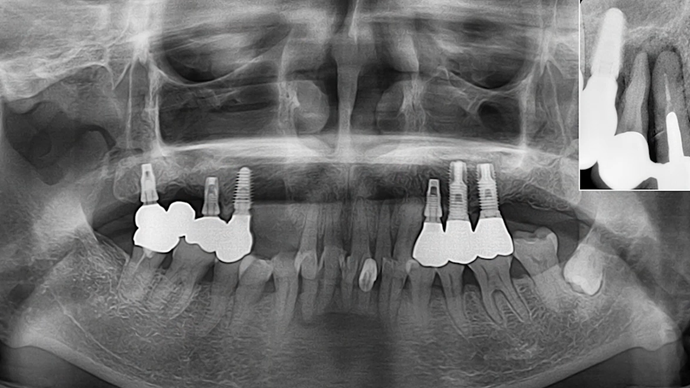

Clinical case: Preview the final goal first, make the ideal treatment plan, then realize it using the appropriate tools

- Courtesy of Dr. Sang Tack Lee, Korea -

Dr. Sang Tack Lee, edentulous, digital full mouth prosthetics, digital guided surgery, #11, #13, #14, #16, #17, #21, #23, #24, #26, #27, #33, #34, #36, #37, #43, #44, #46, #47, guided surgery, flapless, AnyRidge, R2GATE, Mega ISQ, MEG Torq, MEG Engine, R2GATE Full surgical kit

AnyRidge implant system, R2GATE Guide, R2GATE full surgical kit , Mega ISQ